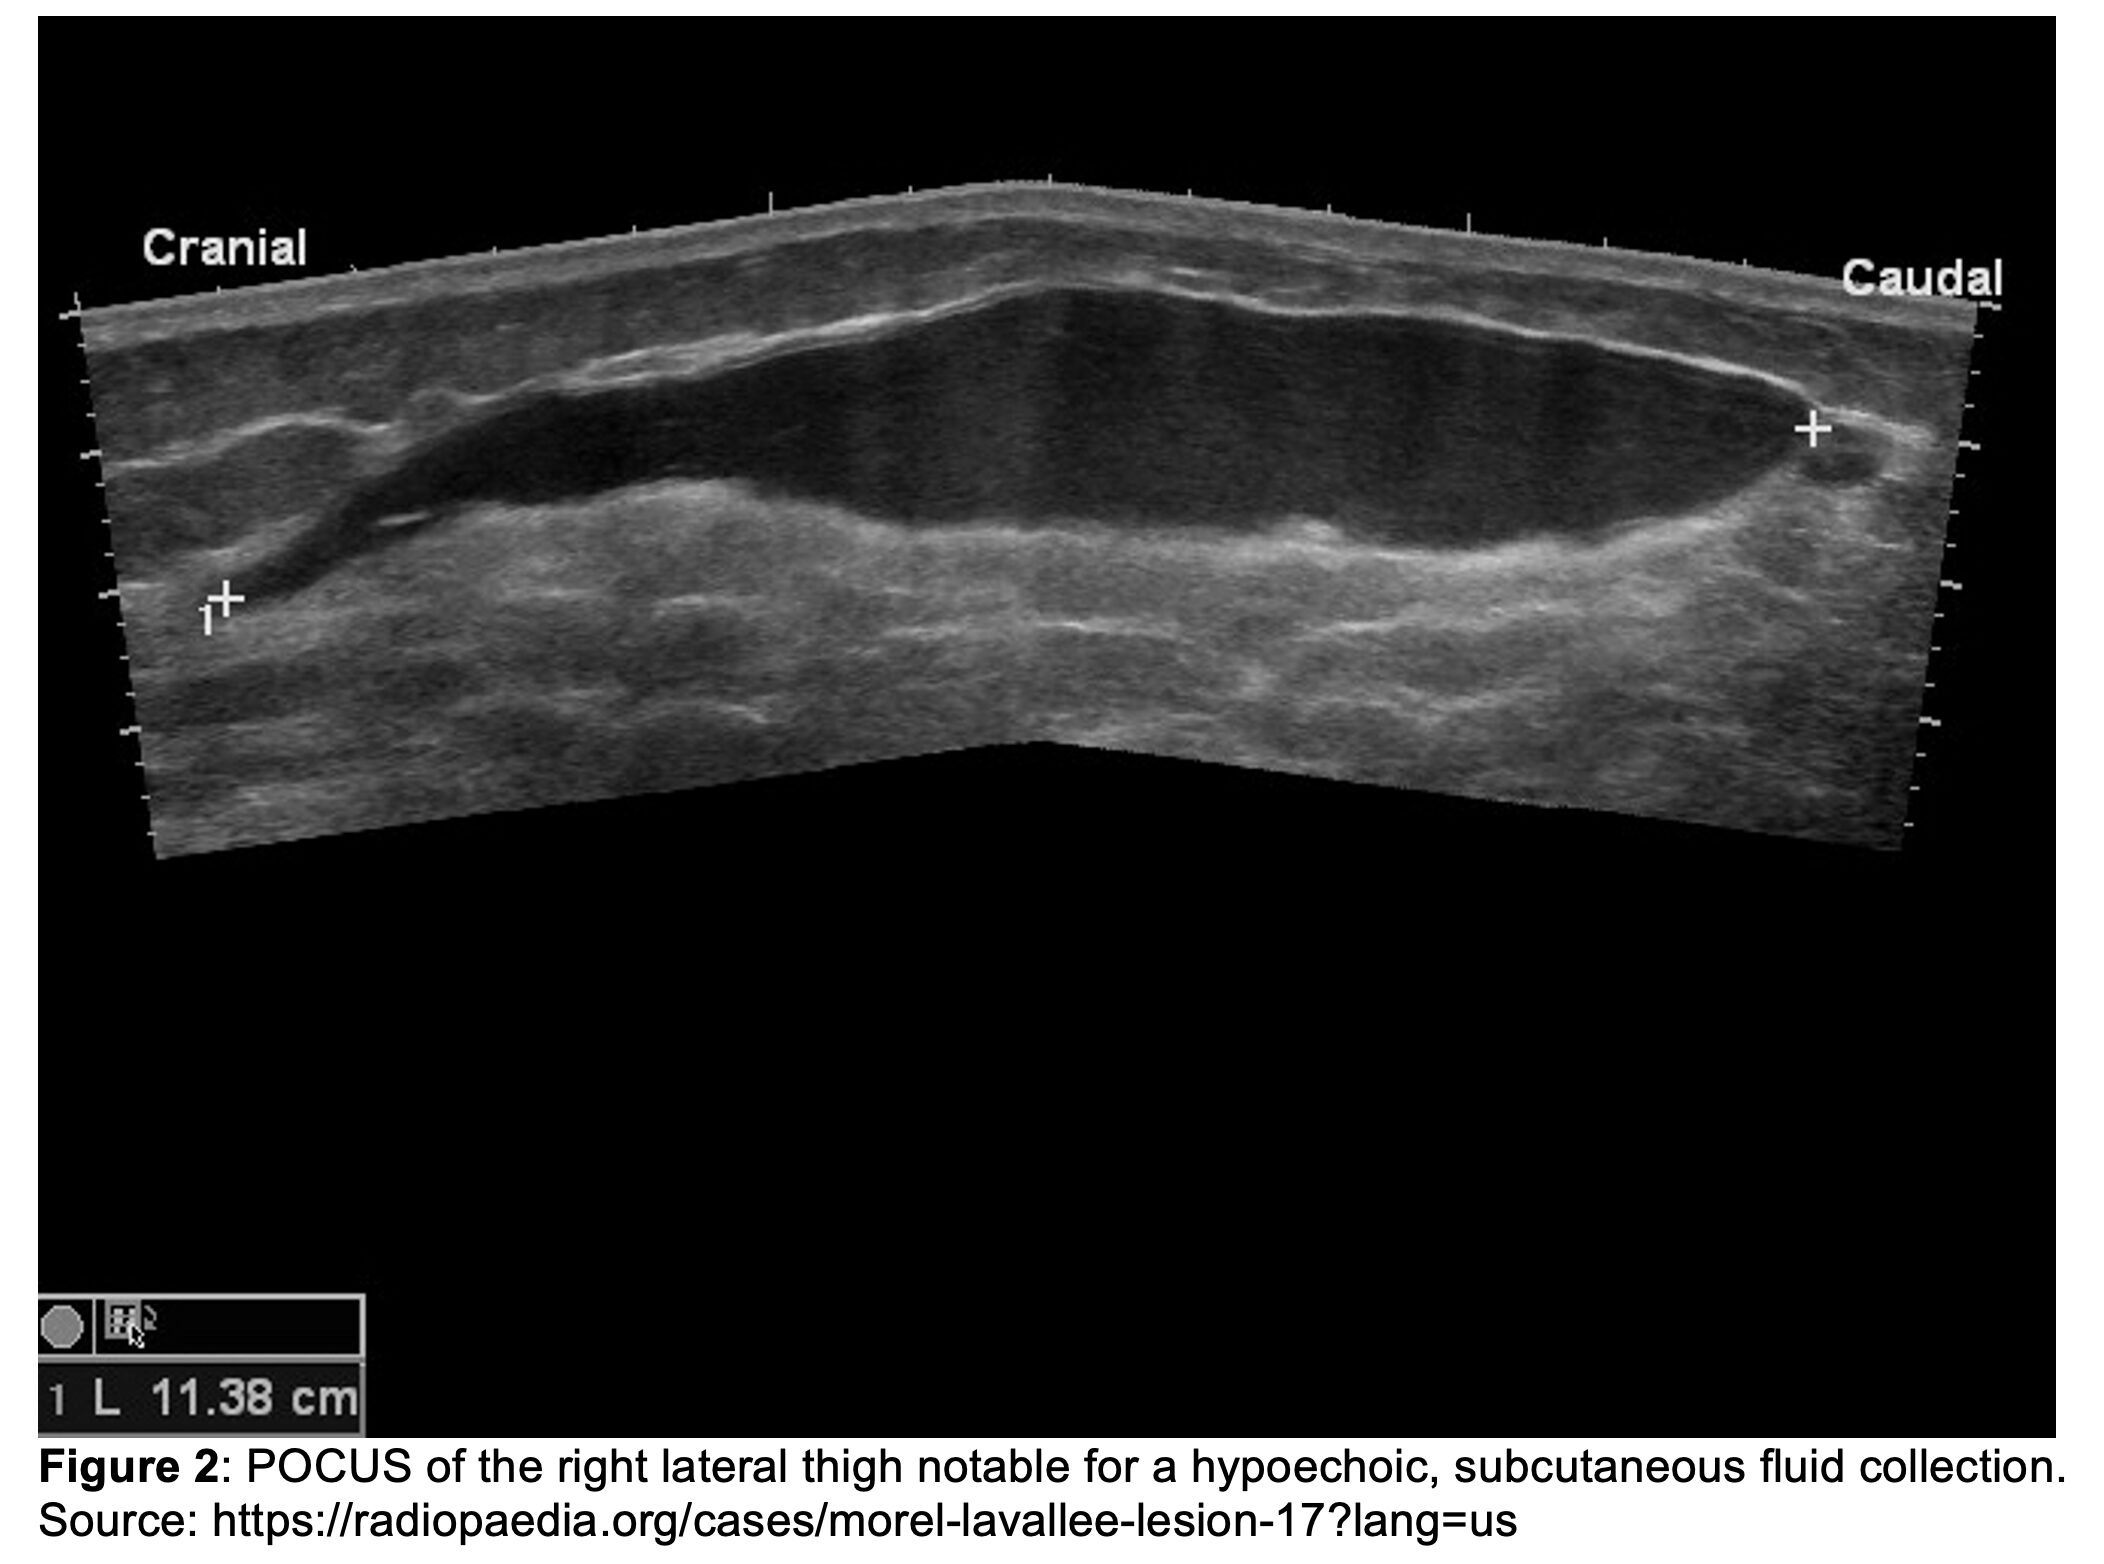

Initial vital signs are notable for BP 93/78 mmHg, HR 122 bpm, T 98.1°F, RR 26/min, and SpO₂ 97% on room air. She is alert with a GCS of 15 but appears in acute distress secondary to pain. Primary trauma survey reveals an intact airway, bilateral breath sounds, and symmetric 1+ distal pulses in all extremities. Bedside imaging of the chest, pelvis, and femur, as well as an eFAST exam, are unremarkable. During the secondary survey, a rapidly expanding mass is noted over the right lateral thigh (Figure 1). The overlying skin is tense and tender to palpation. Point-of-care ultrasound (POCUS) of the region is obtained to further characterize the swelling (Figure 2).

- POCUS9-10

- Useful as an initial diagnostic tool

- Color Doppler may show active bleeding

Clinically, patients often present with a fluctuant, soft, and sometimes painful mass that may enlarge over time. Skin over the lesion may appear normal or ecchymotic, but is usually intact. In the acute setting, plain radiographs are often unrevealing. Point-of-care ultrasound can detect a hypoechoic or anechoic collection superficial to the muscle fascia. MRI is the gold standard for diagnosis, particularly when the lesion is chronic or organizing, as it can help distinguish it from abscess, hematoma, and soft-tissue tumor.